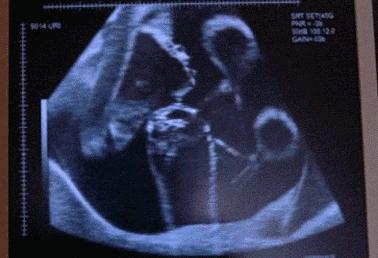

28岁的田女士与丈夫结婚已经6年了,记得在结婚那时,夫妻俩人就开始了造人计划并在不久就传来喜讯,可这样的欢乐没持续多久,在怀孕23周的时候,田女士肚子突然腹痛,而且阴道有出血的症状,家人赶紧把田女士送到医院,然而检查发现胎儿已经胎死腹中两周了。

这噩耗让夫妻俩难以接受,但是也无可奈何。直到一年后再次怀孕,为防意外再次出现,在得知怀孕后就辞职在家。可噩耗再次降临在她身上,宝宝又一次的胎死腹中,接一连二的打击让田女士崩溃了。

“为什么两个孩子都无故就没了,这到底是因为什么?”田女士哭诉。医生对田女士这一情况也非常的疑惑,但是却也找不到病因。

但是在给田女士做清宫手术时,发现她体内的指标有些异常,不仅血压高、甲状腺功能、血钾低,并且在怀孕后就出现皮肤紫纹、痔疮的症状,经一系列的检查,最终找到孩子死亡的原因—脑垂体微腺瘤。

医生表示脑垂体肿瘤一般是育龄妇女患上比较多,如果在得知患有脑垂体肿瘤的女性,一定要及时手术治疗。并且除了脑垂体微腺瘤的疾病使胎儿胎死腹中,孕妇在孕期也要关注这些隐患,才能保证宝宝的顺利降生。